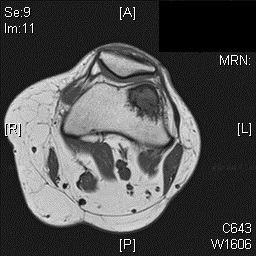

MRI

• MR Imaging, demonstrates intermediate to hypointense signal on T1-weighted images (Fig. 4 & 5) and hyperintensity on T2-weighted images (Fig. 6 & 7).

• Most cases show an extraosseous mass and cortical disruption on MRI.

Fig. 4

Fig. 4 & 5: MR Imaging. Axial (Fig. 4) and Coronal (Fig. 5) T1 weighted image demonstrates a well-defined T1 hypointense mass within the femur with a more hypointense border corresponding to the sclerosis noted on the CT